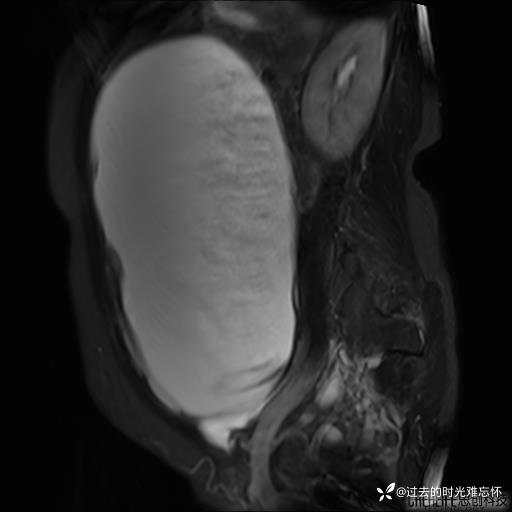

腹大能容5000液;术后腹部好轻松。妙手回春有结果。公布结果。

患者性别:女

患者年龄:65岁

主诉: 发现腹部隆起半年余。无其他明显不适。

浆液性囊腺瘤 (22)